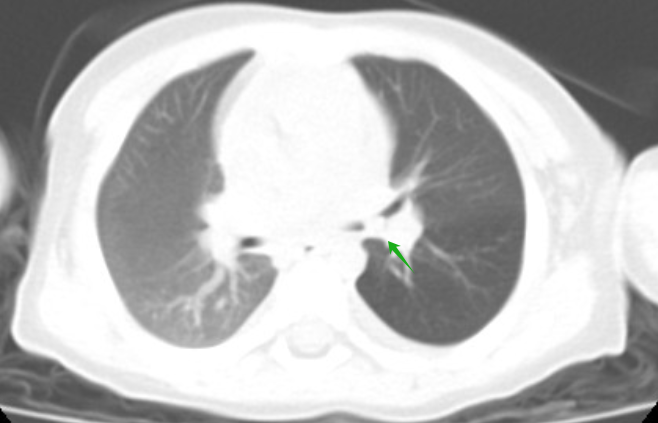

小炫,男,11岁9月,因反复咳嗽5年入院,完善胸部CT检查,影像学诊断右主支气管近段管腔内金属影,遂入院行“支气管镜气管异物取出术+肺泡灌洗术”,术中取出一枚锈迹斑斑的图钉,术后咳嗽症状消失。

(绿色箭头为异物)